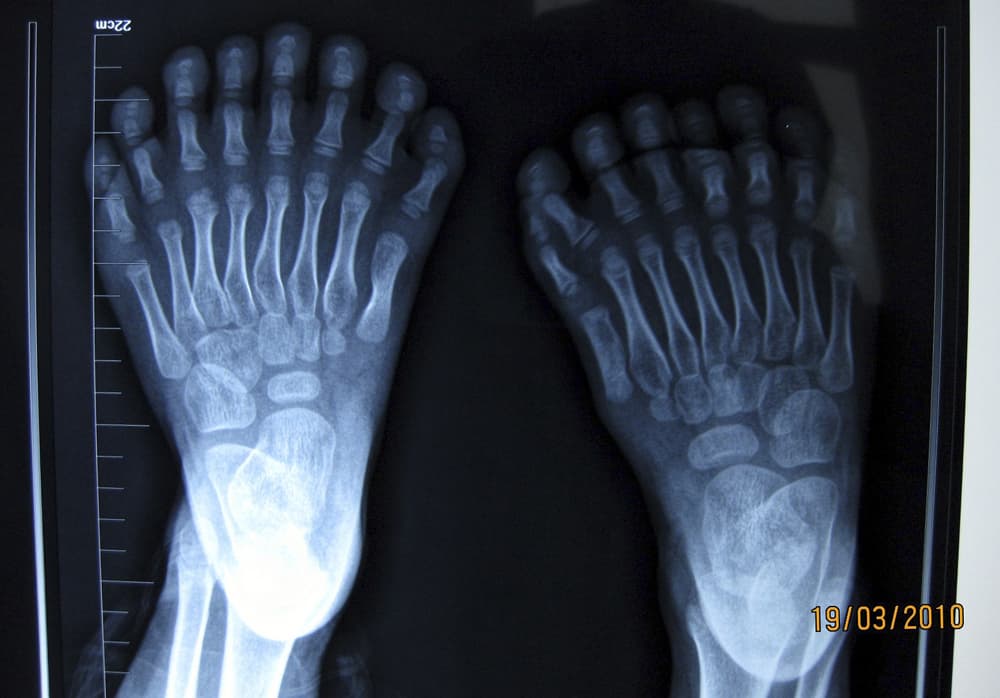

فتى صيني (6 أعوام) يظهر للإعلام أصابع يديه وقدميه -15 أصبع في اليد و 16 أصبع في القدم- داخل مستشفى شنيانغ الذي ستجرى بداخلة عملي